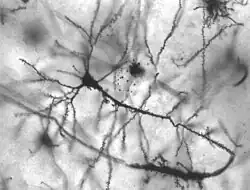

Neurons in person with epilepsy, 40x magnified

Ideally, a neurological disorder is any disorder of the nervous system. Structural, biochemical or electrical abnormalities in the brain, spinal cord, or other nerves can result in a range of symptoms. Examples of symptoms include paralysis, muscle weakness, poor coordination, loss of sensation, seizures, confusion, pain, tauopathies, and altered levels of consciousness. There are many recognized neurological disorders; some are relatively common, but many are rare.